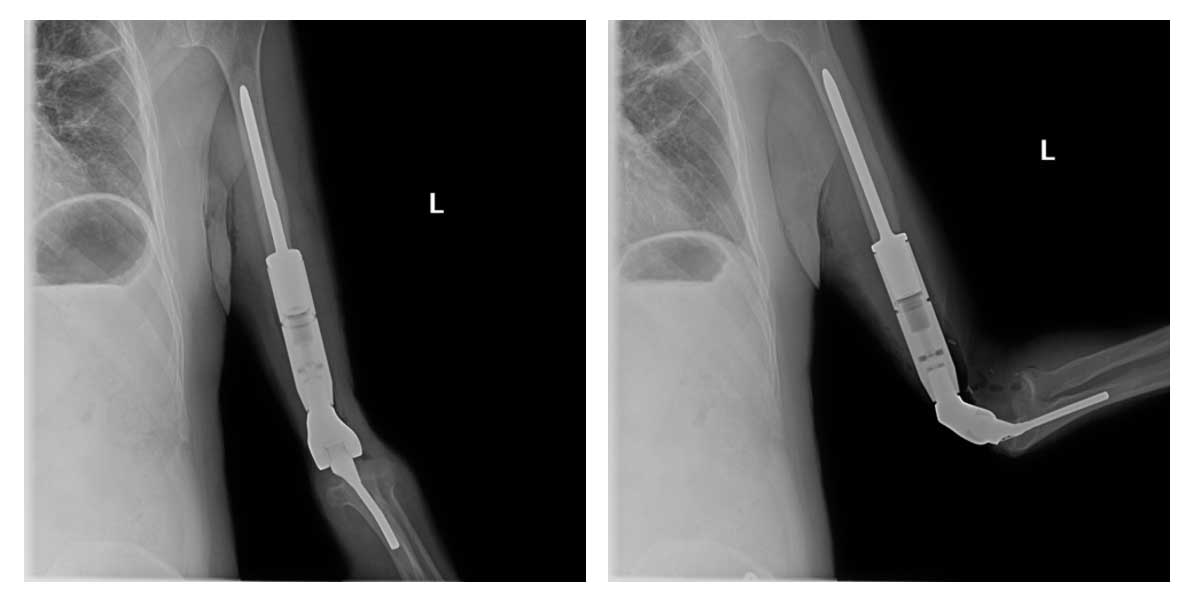

Ameliyat Sonrası: Röntgende çimentolu distal humerus protezinin uygulanımı görülmekte.